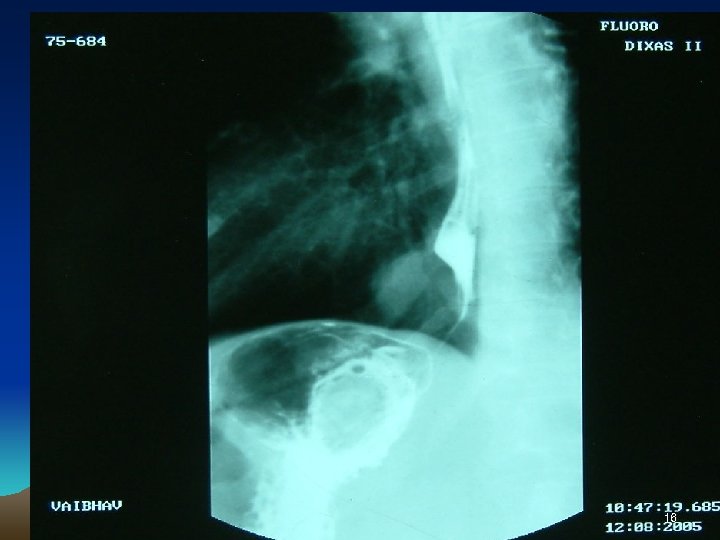

Investigations • • • Chest X Ray USG CECT EUS Ba Swallow 3

4

5

6

7